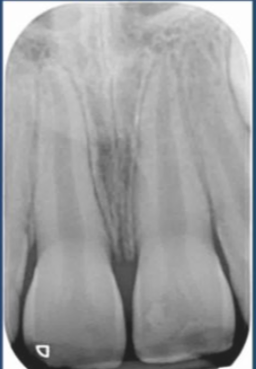

what is shown on this picture?

periacpical granuloma